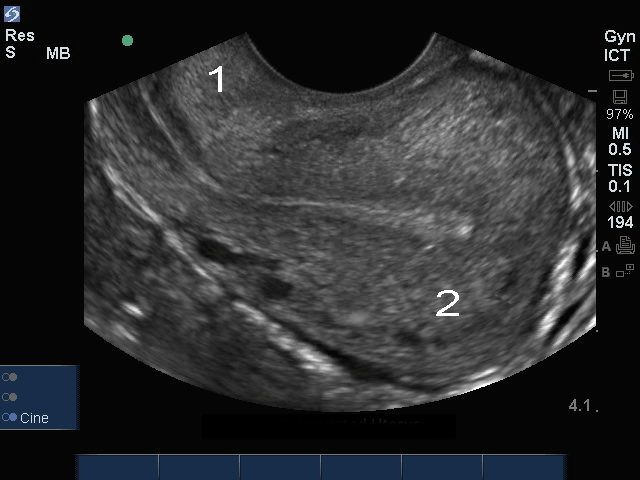

Image : Échographie pelvienne endovaginale, endomètre

Utérus rétroversé

Col Ut

Fond